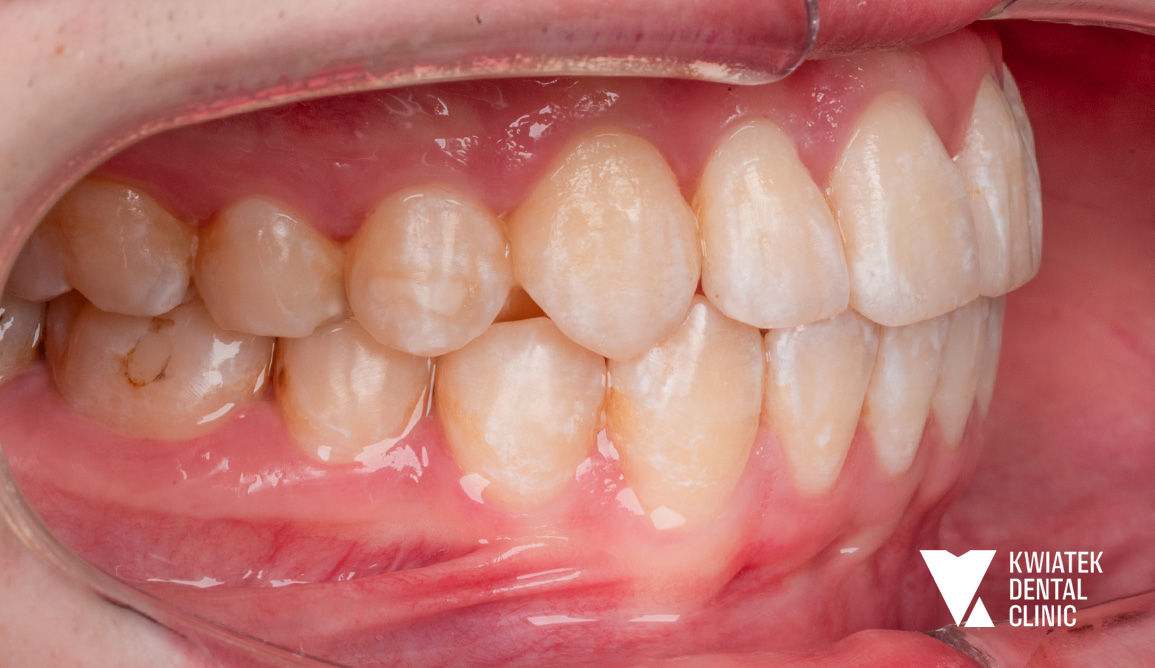

Pełna rekonstrukcja zwarcia i estetyki - historia wymagającej metamorfozy

Pacjent zgłosił się do kliniki z zaawansowanymi problemami stomatologicznymi: licznymi ubytkami próchnicowymi, brakami zębowymi, starciem zębów oraz zaburzeniami zwarcia. Leczenie obejmowało kompleksową diagnostykę, leczenie zachowawcze i endodontyczne, zabiegi chirurgiczne, implantację oraz wieloetapową odbudowę protetyczną. Efektem terapii jest perfekcyjnie zbalansowany zgryz, najwyższy komfort funkcjonowania oraz naturalnie piękny uśmiech, który podkreśla indywidualny charakter pacjenta i pozwala mu w pełni cieszyć się nim każdego dnia.